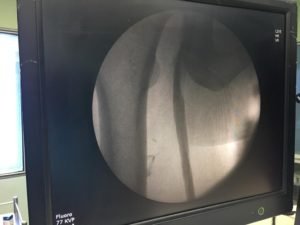

- Pharmacomechanical thrombectomy